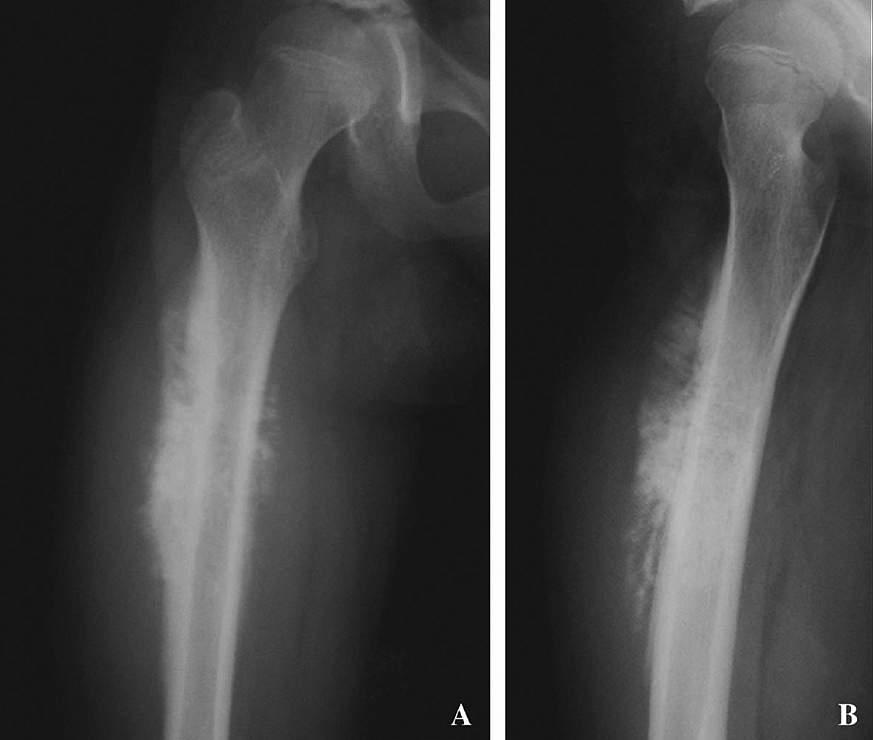

An x-ray of a femur from a patient with osteosarcoma

An x-ray of a femur (thigh bone) from a patient with osteosarcoma. Ups J Med Sci.